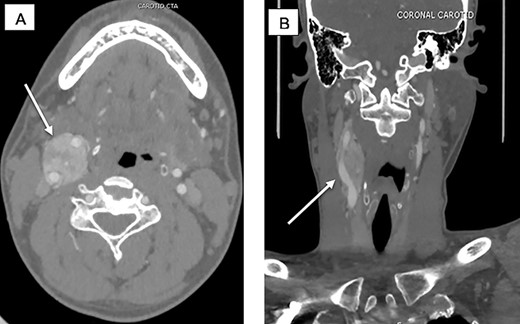

A 32-year-old male referred for surgical evaluation of an asymptomatic, 7 cm, right neck mass. There was no family history of paragangliomas or evidence of multiple paragangliomas. Initial work up included a bilateral neck ultrasound that showed a hypervascular, hypoechoic mass on the right carotid artery bifurcation. Then, a computed tomography angiography (CTA) was done and showed the tumor encasing the carotid vessels, including the bifurcation consistent with a Shamblin III CBT (Fig. 1). Biochemical testing with 24-h urine catecholamines was negative.

(A) CTA sagittal view, white arrow pointing to the CBTs encasing the ICA and ECA corresponding to Shamblin III. (B) CTA coronal view, white arrow pointing at the CBTs.